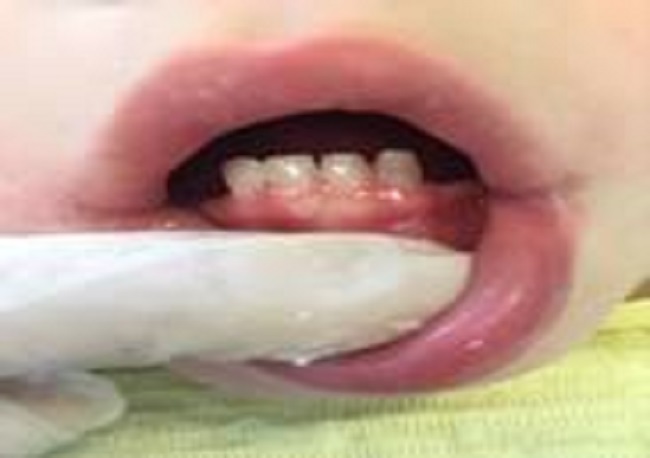

Al examen clínico de la cavidad bucal (Figuras 2, 3 y 4) no se observaron lesiones en las mucosas, se certificaron quince dientes temporarios ausentes (55-54-52-51-61-62-63-64-65-73-74-75-83-84-85) y cinco dientes temporarios con lesiones de caries (53-71-72-81-82); presencia generalizada de biopelícula sobre las superfícies dentarias, sangrado gingival provocado al sondaje, saliva abundante, lengua voluminosa, desbordante e hipotónica y bridas y frenillos sin particularidades.